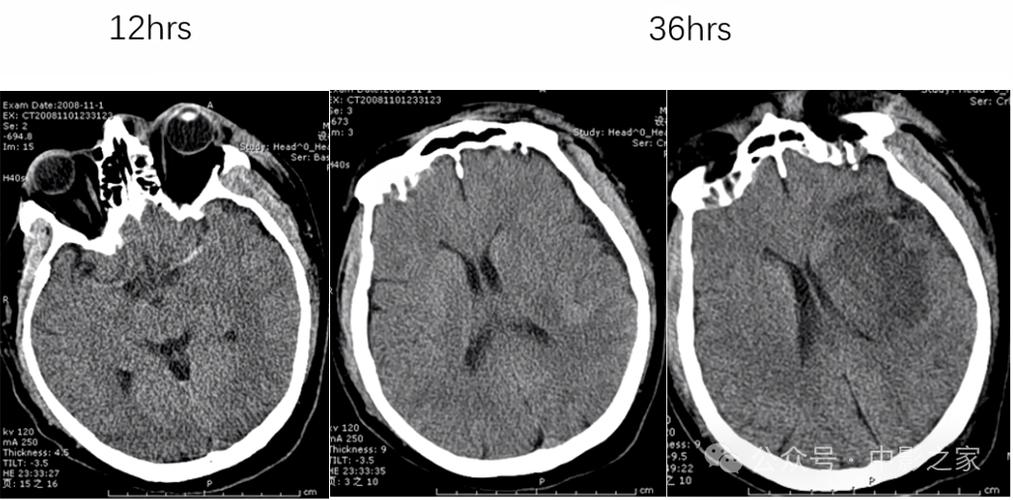

在脑梗发生的早期(通常在6小时内),普通的CT扫描很难直接显示出脑梗的病灶,因为在这个阶段,脑组织只是缺血,细胞水肿还非常轻微,密度变化不大,CT上可能完全正常,或者只有一些非常细微、难以察觉的征象。

如果发病时间超过6-24小时,随着脑细胞开始死亡、水肿加重,CT上就可能出现一些异常信号,医生可以据此判断脑梗的可能性,这些早期间接征象包括:

- 脑沟变浅或消失:由于脑组织水肿,导致脑表面的沟回变浅。